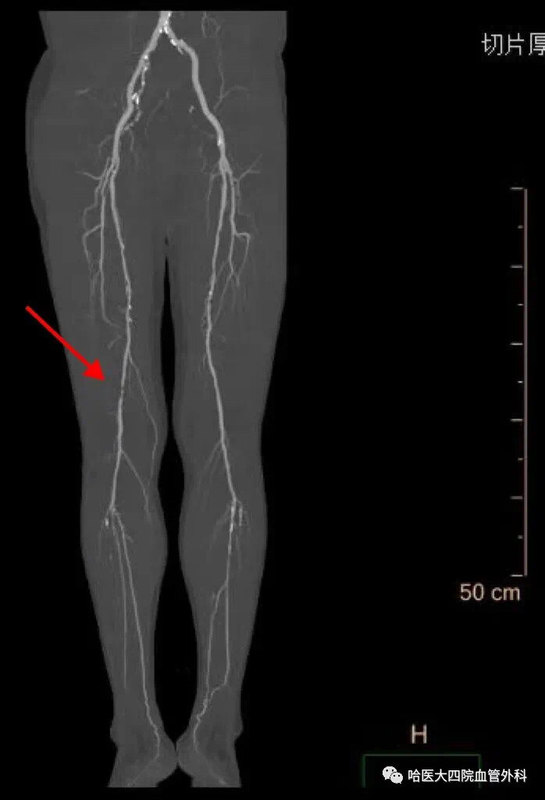

哈醫(yī)大四院血管外科完成省內(nèi)首例準(zhǔn)分子激光消蝕減容術(shù)治療下肢動(dòng)脈硬化閉塞癥

聽說過激光能祛斑、祛疤、治近視眼,您聽說過激光還可以通血管么?日前,哈醫(yī)大四院血管外科應(yīng)用準(zhǔn)分子激光設(shè)備,率先在省內(nèi)成功為一位高齡下肢動(dòng)脈硬化閉塞癥患者開通閉塞血管,完成我省首例應(yīng)用準(zhǔn)分子激光消蝕減容術(shù)治療下肢動(dòng)脈硬化閉塞癥的手術(shù)。謝大娘今年80歲,半年前自覺右下肢疼痛,麻木,皮溫涼,跛行距離100米,未進(jìn)行治療。半月前疼痛加重,出現(xiàn)患足靜息痛,跛行距離僅為10米,且夜間疼痛明顯加重,嚴(yán)重影響生活質(zhì)量。家屬帶謝大娘來到哈醫(yī)大四院血管外科,黃任平主任接診后通過下肢動(dòng)脈CTA發(fā)現(xiàn)患者右側(cè)股總動(dòng)脈、股淺動(dòng)脈閉塞,考慮患者癥狀明顯,如不進(jìn)行手術(shù)干預(yù),缺血加重可能會(huì)導(dǎo)致肢體壞疽,截肢可能。經(jīng)過縝密的術(shù)前討論,黃任平主任決定采用我院剛剛引進(jìn)的準(zhǔn)分子激光設(shè)備為患者開通病變血管。黃任平主任團(tuán)隊(duì)為患者實(shí)施手術(shù),通過左側(cè)股動(dòng)脈穿刺翻山至右側(cè),導(dǎo)入準(zhǔn)分子激光導(dǎo)管,對閉塞動(dòng)脈血管進(jìn)行消融,消融后即刻可見血管恢復(fù)通暢。然后導(dǎo)入藥物涂層球囊擴(kuò)張,再次血管造影可見股腘動(dòng)脈通暢,血液流速快,術(shù)后患者足背及脛后動(dòng)脈搏動(dòng)恢復(fù),右下肢靜息痛消失,跛行癥狀明顯緩解,目前患者已經(jīng)康復(fù)出院。黃任平主任介紹,準(zhǔn)分子激光消蝕術(shù)(ExcimerLaserAtherectomy,ELA)是一種在歐美國家常規(guī)使用的冠脈介入治療手段,應(yīng)用準(zhǔn)分子激光治療下肢動(dòng)脈硬化閉塞癥在國外已經(jīng)開展多年,在我國開展較晚,該手術(shù)在我省尚屬首例。其原理是在光化學(xué)作用下,斑塊組織對308nm激光能量的吸收可引起分子鍵的斷裂,碎化成直徑小于25um的碎片,因此該準(zhǔn)分子激光可以安全消蝕溶解血管內(nèi)的血栓、斑塊等組織,更有效的開通閉塞的血管,同時(shí)能夠保證開通血管的遠(yuǎn)期通暢率,減少了支架的植入。該技術(shù)適合在下肢動(dòng)脈硬化閉塞癥,血栓閉塞性脈管炎,以及支架再閉塞等嚴(yán)重下肢缺血患者治療中應(yīng)用。?????????????專家簡介??????????????????????黃任平醫(yī)學(xué)博士、博士后,碩士生導(dǎo)師哈爾濱醫(yī)科大學(xué)附屬第四醫(yī)院血管外科主任???專業(yè)方向:擅長血管外科的常見病多發(fā)病的診治,從事微創(chuàng)血管病治療與創(chuàng)面治療10余年,治愈各種靜脈曲張、糖尿病足、下肢靜脈血栓、脈管炎、動(dòng)脈硬化閉塞癥、胸腹主動(dòng)脈瘤、動(dòng)脈栓塞、肺栓塞、鎖骨下動(dòng)脈閉塞、腎動(dòng)脈狹窄、嬰幼兒血管瘤、血管畸形等20000余例。出診地點(diǎn):哈爾濱醫(yī)科大學(xué)附屬第四醫(yī)院門診三樓C區(qū)外科3診室咨詢電話:0451-82576869